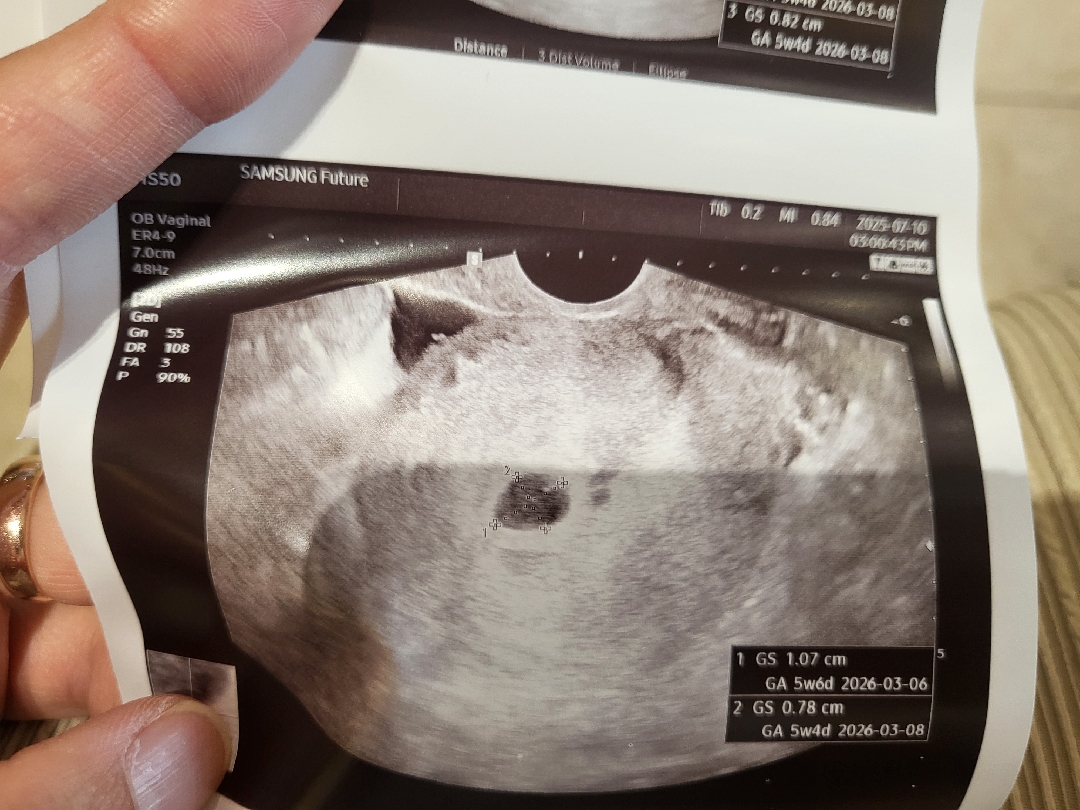

막생 6월7일이구 임테기로 임신확인하구 꾹 참다가 오늘 병원갔다왔어요!! 아기집보고왓는데 기분이 묘하네요 ㅠㅠ(셋째예요^^)ㅎㅎ 근데 살딱 피고임이 보인다해서 걱정인데 ㅠㅠ괜찮겟죠?ㅠㅠ의사 말론 괜찮다고 하는데 ㅠㅠ걱정이내요 ㅠㅠ